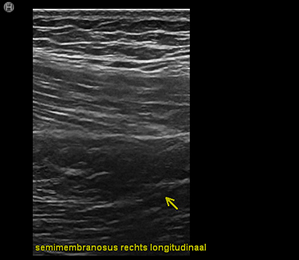

Orthopedische echografie, een blessure nader bekeken .........

Wij beschikken over mobiele echo-apparatuur met haarscherp beeld!